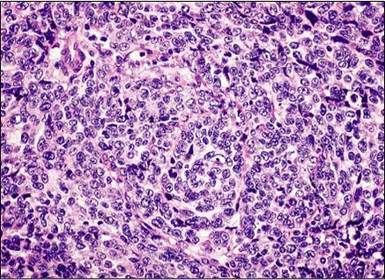

Qual é o aspecto da célula? Formam microfolículos chamados de? Células em "grão de café", corpúsculos de Call-Exner.

DIAGNÓSTICO. Qual é o marcador tumoral dessa neoplasia? Tumor de células da granulosa. Alfa-inibina.